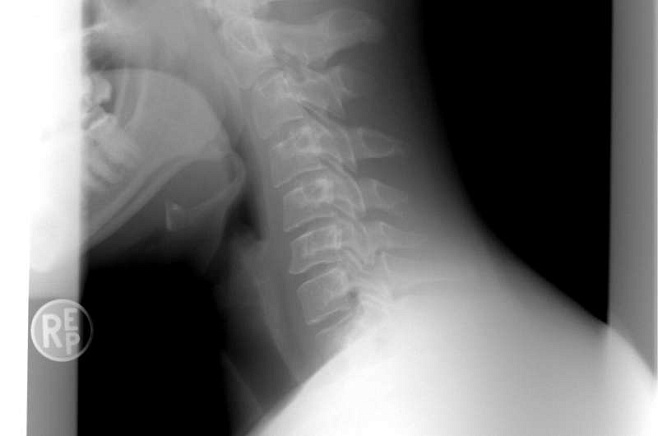

Новое устройство определяет шейную патологию по движению пальцев

Метод, разработанный учёными, основан на комбинации машинного обучения и анализа движений пальцев с помощью бесконтактного датчика. Технология была протестирована на пациентах с шейной миелопатией: участники совершали захваты пальцами, а устройство считывало, насколько трудно им это делать.

Сенсор Leap Motion в сочетании с алгоритмом машинного обучения позволит точно диагностировать шейную миелопатию на ранних стадиях не только специалистам, но и простым гражданам. Автоматическая система сама определяет склонность человека к патологии и её степень.